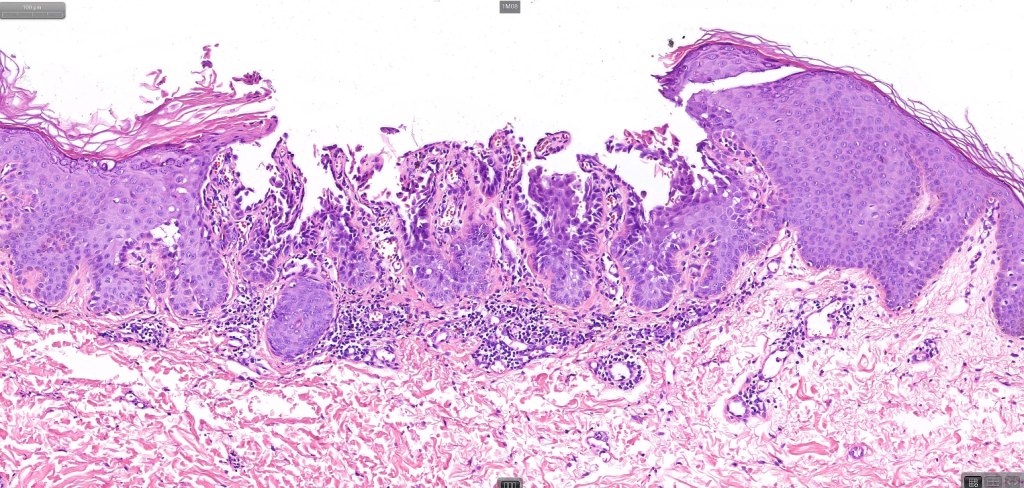

•Cup-shaped, cystic invagination containing keratinous debris showing conspicuous corps ronds & grains of Darier

•The deeper reaches show acantholysis and prominent suprabasal villi